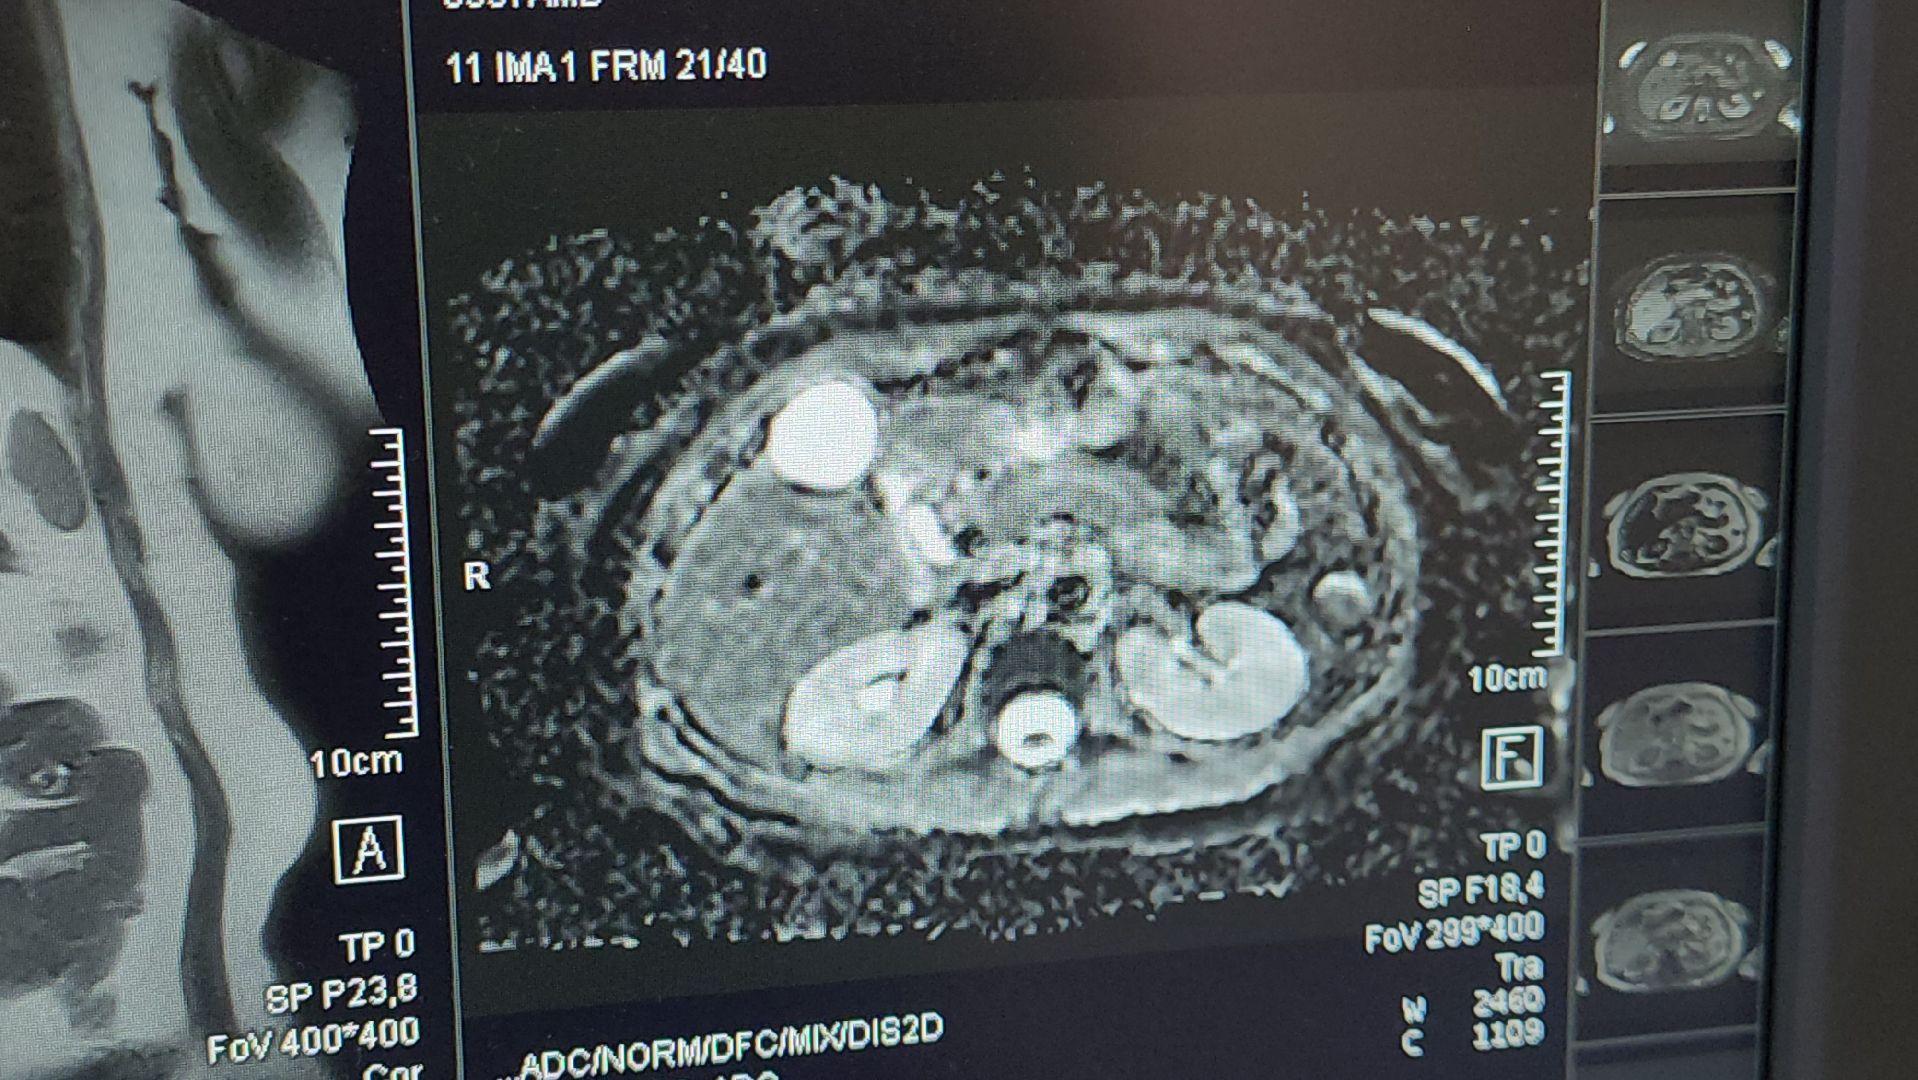

С момента подключения аппарата выполнили 737 исследований. Как отметил Игорь Нараев, в основном это исследования позвоночника и головного мозга, на третьем месте — коленные суставы.